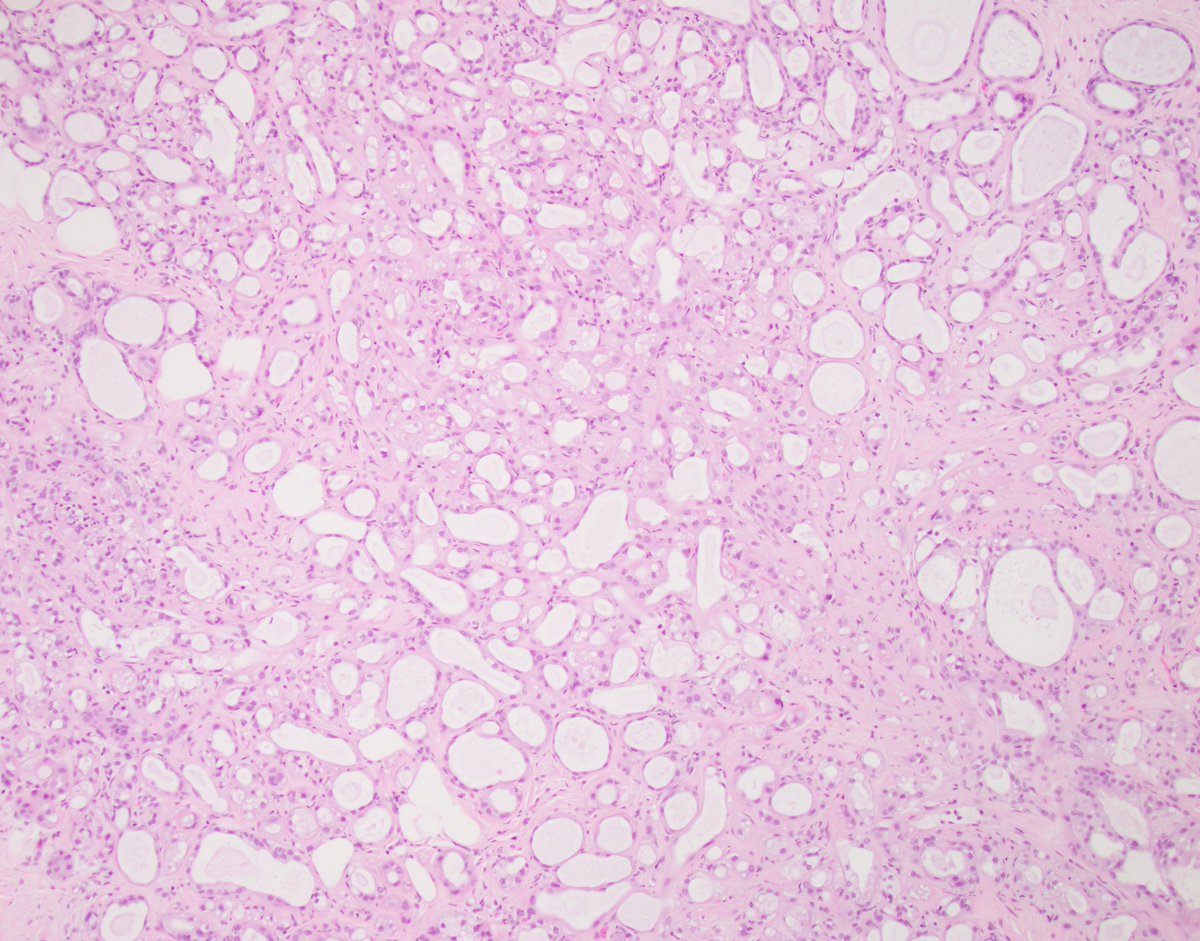

Breast Consult Case of the Week 1 #BCCW:

50 year old with non-mass enhancement on MRI.

What is the consulting pathologist's question(s) and what is your interpretation? (third image depicts p63 IHC)

See you Friday! #PathTwitter #PathX @washupathedu @washu_pathology